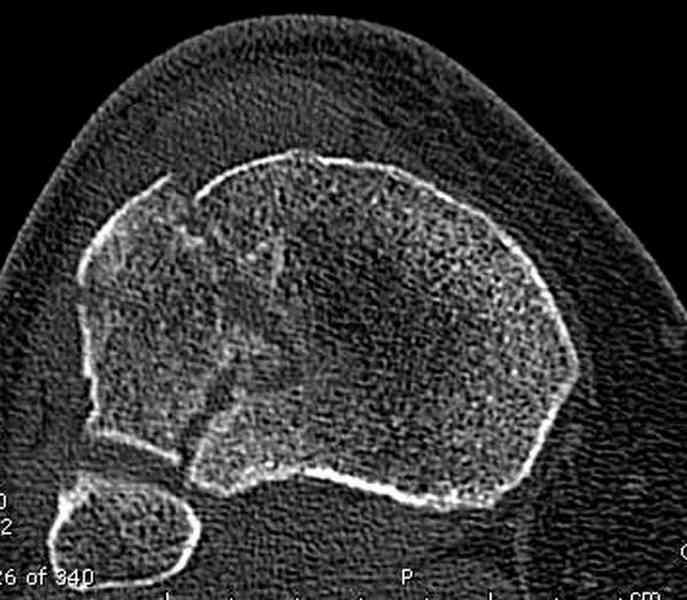

Для внутрисуставных переломов необходимо идеальное сопоставление, а

такая задача без КТ срезов усложнится. Только КТ надо делать после

дистракции сустава, иначе нельзя получить  объективную информацию.

Имя     : 3 lat tib plateau CT2.jpg

Тип     : image/jpeg

Размер  : 53226 байтов

Описание: отсутствует

Url     : http://weborto.net:8080/pipermail/ortho/attachments/20100926/dbcec959/attachment-0014.jpg

Имя     : 4 lat tib plateau CT.jpg

Размер  : 50105 байтов

Url     : http://weborto.net:8080/pipermail/ortho/attachments/20100926/dbcec959/attachment-0015.jpg